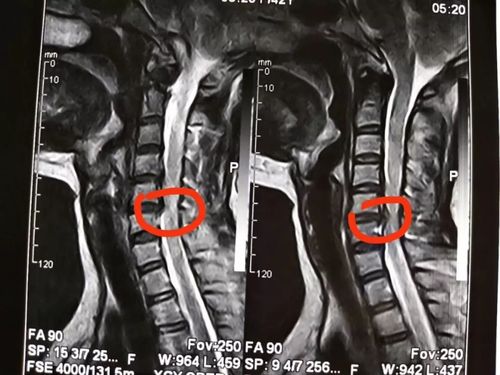

椎管图片,椎管狭窄图片

(正常椎管和椎管狭窄,图片源自网络)

椎管狭窄图片

腰椎管狭窄图片

椎管狭窄图片解析

椎管狭窄